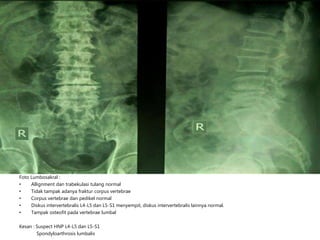

Foto Lumbosakral :

• Allignment dan trabekulasi tulang normal

• Tidak tampak adanya fraktur corpus vertebrae

• Corpus vertebrae dan pedikel normal

• Diskus intervertebralis L4-L5 dan L5-S1 menyempit, diskus intervertebralis lainnya normal.

• Tampak osteofit pada vertebrae lumbal

Kesan : Suspect HNP L4-L5 dan L5-S1

Spondyloarthrosis lumbalis